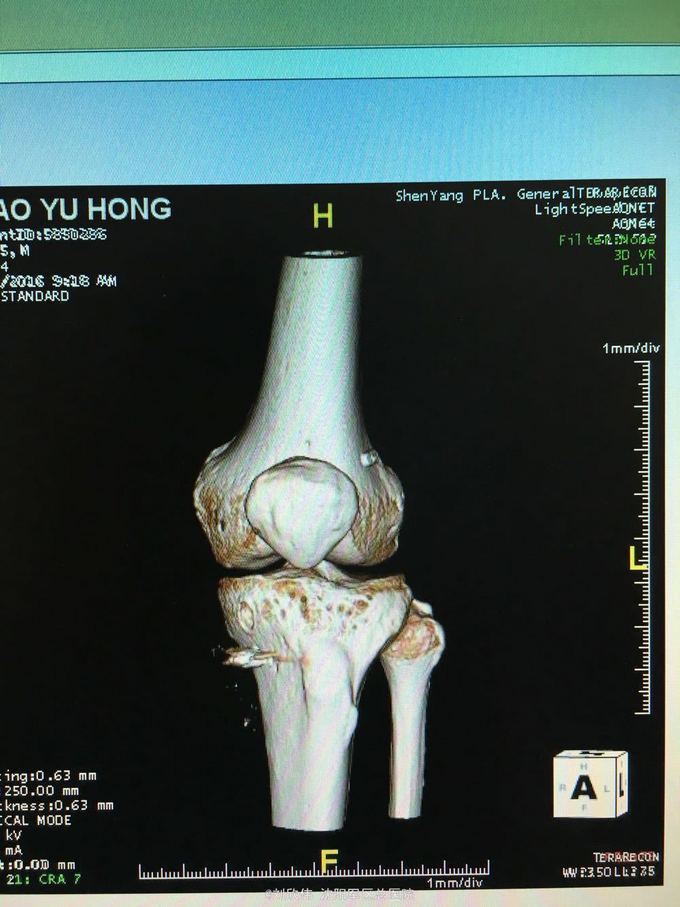

关节镜之前交叉韧带+内侧副韧带损伤1例

男性,44岁,摔伤所致,左膝。诊断如题

前抽屉,lachman,轴移阳性,外侧应力试验因疼痛无法进行

诊断如题,关节镜解决acl,mcl给予支具保守治疗

这个病例值得讨论的有2点,其一,mcl即内侧副韧带的处理通常可以保守治疗,二期不稳后再行手术治疗。第二,前叉胫骨侧隧道内口的位置,一个原则,宁内勿外。